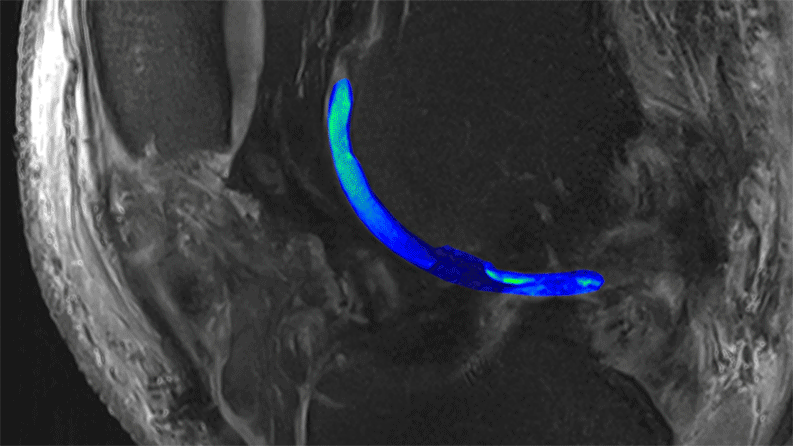

MRT-Bild

Das traditionelle MRT verwendet magnetische Impulse, um ein Signal von Wassermolekülen im Körper zu induzieren. Diese Technologie hebt den Knorpel (blau/hellgrün) visuell vom Knochen ab. Ein fortgeschrittenes MRT hat zwar den gleichen Ansatz, wendet ihn aber auf Natrium anstelle von Wassermolekülen an. Sie macht Proteoglykane (hellgrün), den besonderen Bestandteil eines hochwertigen Knorpels, sichtbar. Regionen ohne dieses Natriumsignal deuten auf einen defekten Knorpel hin. Bilder mit freundlicher Genehmigung von Siegfried Trattnig (modifiziert von Fidelis Onwubueke)

Zusätzlich zum Einsatz eines leistungsstarken MRT-Gerätes hat Trattnig Techniken entwickelt, die das Spektrum der Materialien erweitern, die MRT-Geräte erfassen können. So kann die Technologie beispielsweise den Proteoglykanspiegel, den besonderen Bestandteil eines hochwertigen Knorpels, eruieren.

Diese MRT-Aufnahmen zeigen auch Spalten im Knorpel (oben in dunklerem Blau), die auf eine Schädigung hinweisen. NIBR Forscher untersuchen, wie sie diese Lücken mit hochwertigem Knorpel im Zuge experimenteller Regenerations-Medizin schliessen können. Durch den Einsatz fortschrittlicher MRT in ihren klinischen Studien könnten sie einen Weg gefunden haben, die Qualität regenerierten Knorpels messen können – und all das ohne die Patienten einer schmerzhaften Biopsien auszusetzen.